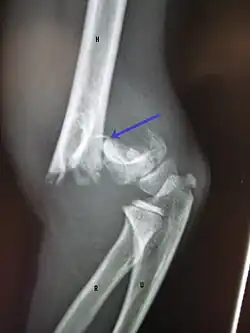

A displaced supracondylar fracture in a child

Distal humerus fractures usually occur as a result of physical trauma to the elbow region. If the elbow is bent during the trauma, then the olecranon is driven upward, producing a T- or Y-shaped fracture or displacing one of the condyles.[7]

Fractures of the humerus are classified based on the location of the fracture and then by the type of fracture. There are three locations that humerus fractures occur: at the proximal location, which is the top of the humerus near the shoulder, in the middle, which is at the shaft of the humerus, and the distal location, which is the bottom of the humerus near the elbow.[9] Proximal fractures are classified into one of four types of fractures based on the displacement of the greater tubercle, the lesser tubercle, the surgical neck, and the anatomical neck, which are the four parts of the proximal humerus, with fracture displacement being defined as at least one centimeter of separation or an angulation greater than 45 degrees. One-part fractures involve no displacement of any parts of the humerus, two-part fractures have one part displaced relative to the other three; three-part fractures have two displaced fragments, and four-part fractures have all fragments displaced from each other.[13][14][3] Fractures of the humerus shaft are subdivided into transverse fractures, spiral fractures, "butterfly" fractures, which are a combination of transverse and spiral fractures, and pathological fractures, which are fractures caused by medical conditions.[12] Distal fractures are split between supracondylar fractures, which are transverse fractures above the two condyles at the bottom of the humerus, and intercondylar fractures, which involve a T- or Y-shaped fracture that splits the condyles.[7]